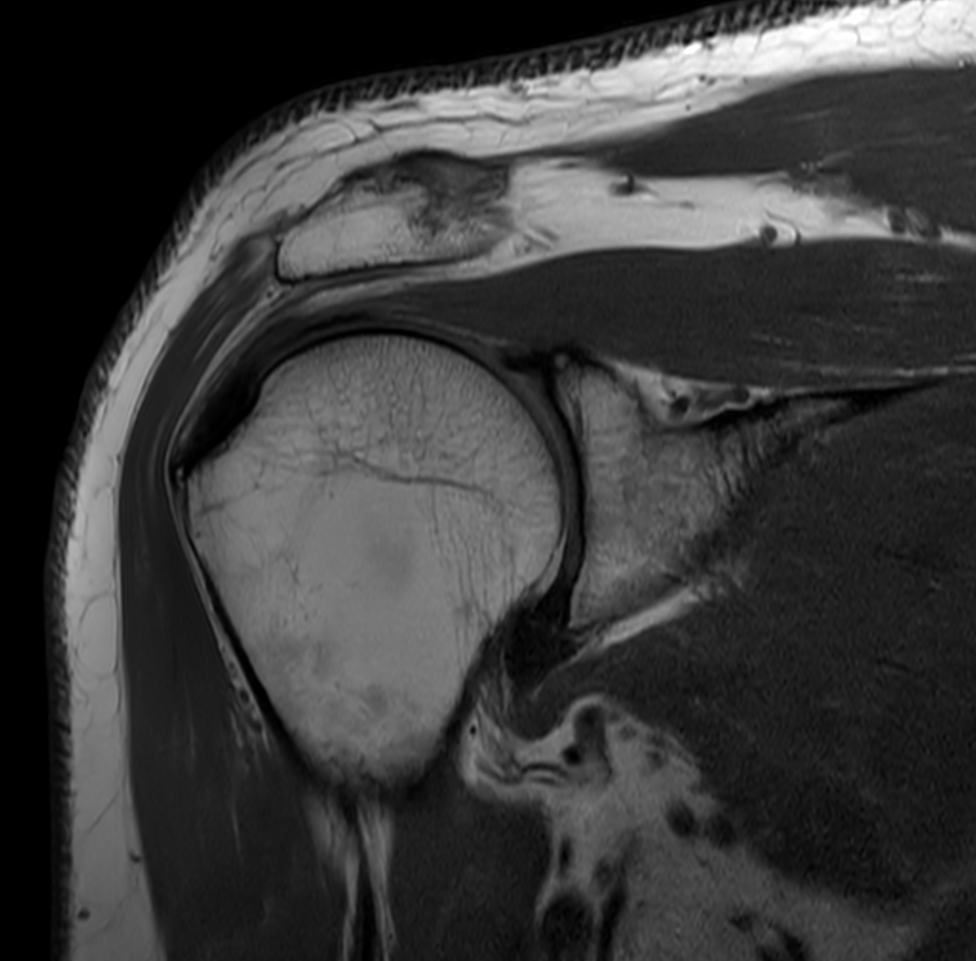

High resolution imaging with the dS 16ch Shoulder coil and Compressed SENSE